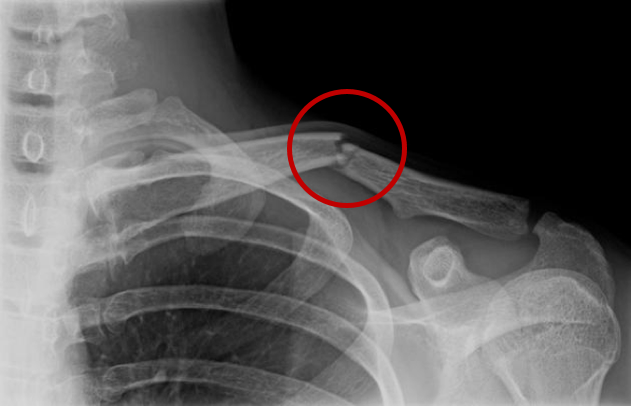

U heeft een breuk in het sleutelbeen (clavicula), waarbij de stand van de botten voldoende is voor een goed herstel. De breuk zit in het middelste deel van uw sleutelbeen. De behandeling bestaat uit een soort draagband (sling), een korte rustperiode en specifieke oefeningen voor de schouder.

Uw breuk zit in het middelste gedeelte van het sleutelbeen. Deze breuk komt vaak voor en dit herstelt meestal zonder problemen. De behandeling bestaat uit een sling, een korte rustperiode en het doen van specifieke oefeningen. Zo heeft u minder pijn, geneest de breuk het snelst en verkleint u de kans op blijvende klachten.